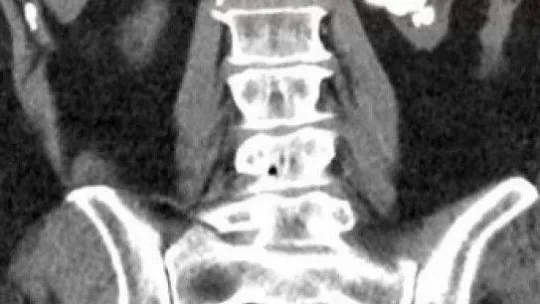

Çanakkale’nin Çan ilçesinde yaşayan Nesibe Işık, 5 gün önce ÇOMÜ Hastanesi Üroloji Bölümü’ne böbrek ağrısı şikayetiyle başvurdu. Nesibe Işık’ın yapılan tetkik ve kontrollerinde böbreğinde büyük bir taş parçası olduğu tespit edildi. Ameliyata karar verildi. Üroloji Bölümü’nden Doç. Dr. Eyüp Burak Sancak ve ekibi tarafından Çanakkale’de ilk kez uygulanan ‘Miniperk’ yöntemiyle Nesibe Işık ameliyat oldu. Işık’ın böbreğini kaplayan taş, parçalandı. Yaklaşık yüz parçaya ayrılan taş parçaları, böbrekte küçük bir delik açılarak alındı.

Nesibe Işık’ın sol böbreğinde böbreğin içerisini tamamen dolduran, bilimsel olarak geyik boynuzu olarak adlandırılan dev böbrek taşı mevcut olduğunu belirten Doç. Dr. Eyüp Burak Sancak, “Hastamızın böbrek fonksiyonları da sınırda çalışmaktaydı. Bu nedenle hastamıza ve böbreğe daha az hasar verecek, Çanakkale’de ilk kez uygulanan ‘Miniperk’ yöntemi ile daha küçük bir delikten böbrek taşlarının tamamını temizledik. Günümüzde teknolojik gelişmeler ve bilimsel yöntemler hep daha az zarar veren, daha küçük kesi ile yapılan cerrahilere doğru değişim göstermekte, biz de ÇOMÜ Hastanesi Üroloji Anabilim Dalı olarak, bu teknolojiye ayak uydurma çabasındayız. Hastalara daha az hasar veren ‘Minimal Invaziv’ olarak adlandırılan yöntemleri uygulamaya çalışıyoruz. Bu nedenle hastamıza çok daha küçük bir delikten, çok büyük olan böbrek taşı alma işlemini yani, ilk kez ‘Miniperk’ yöntemini uyguladık. Hastamızın şu an sağlık durumu gayet iyi, çok kısa zamanda toparlandı” dedi.